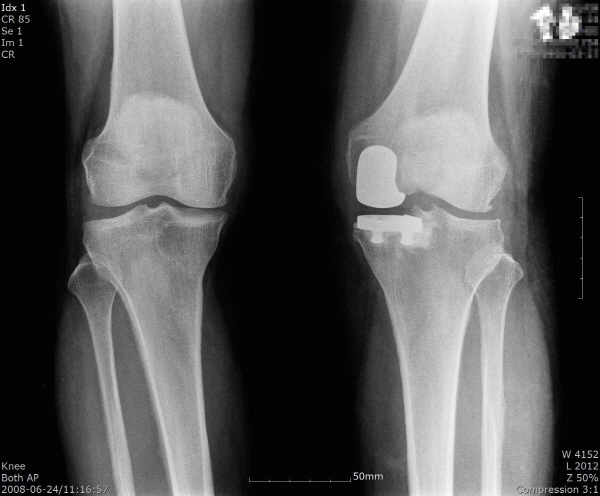

인공관절 수술은 발전을 통해 정확도가 향상된 수술로 자리 잡았지만, 일부 환자들은 연골을 제거하고 인공 구조물로 무릎 관절을 완전히 대체하는 것에 부담을 느끼곤 한다. 따라서 이때는 무릎 관절 전체를 없애는 인공관절 전치환술 대신 손상이 생긴 관절 일부만 인공관절로 교체하는 ‘부분 치환술’을 고려할 수 있다.

건강한 관절을 최대한 보존하는 방향으로 이뤄지는 인공관절 부분치환은 관절 운동의 각도를 살리고 절개나 출혈 없이 진행할 수 있는 특징을 가진다. 기능을 최대한 보존하기 때문에 많은 환자에게 적용되고 있으며, 최근에는 ‘3D 시뮬레이션 맞춤형 부분 치환술’을 이용해 반대편 무릎에 가해지는 하중을 줄여 무릎의 부담을 줄이고, 인공관절 수명의 연장을 기대하는 경우도 늘고 있다.